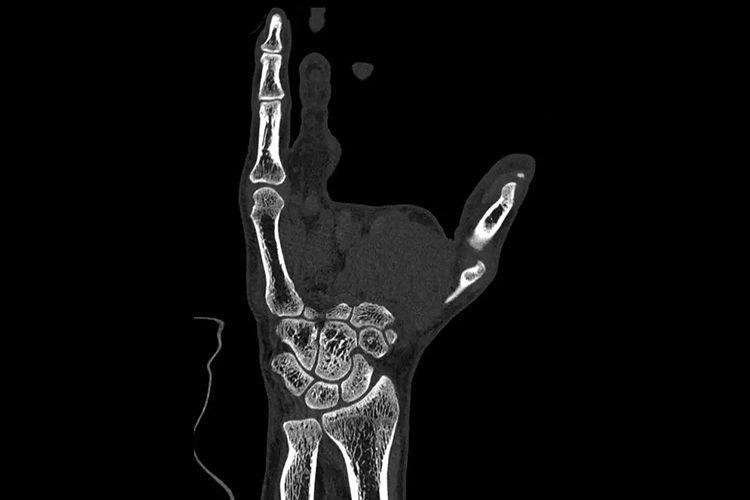

正常成人手骨在CT上可见其形态完好,位置正常,由腕骨、掌骨和指骨构成。腕骨共8块,包括手舟骨、月骨、三角骨和豌豆骨、大多角骨、小多角骨、头状骨和钩骨;掌骨共5块,包括第1-5掌骨;指骨共14块,拇指有2节指骨,其余各指均为3节,分别为近节、中节、远节指骨。手部CT通过CT后处理技术,可清晰看到各部分组织结构。